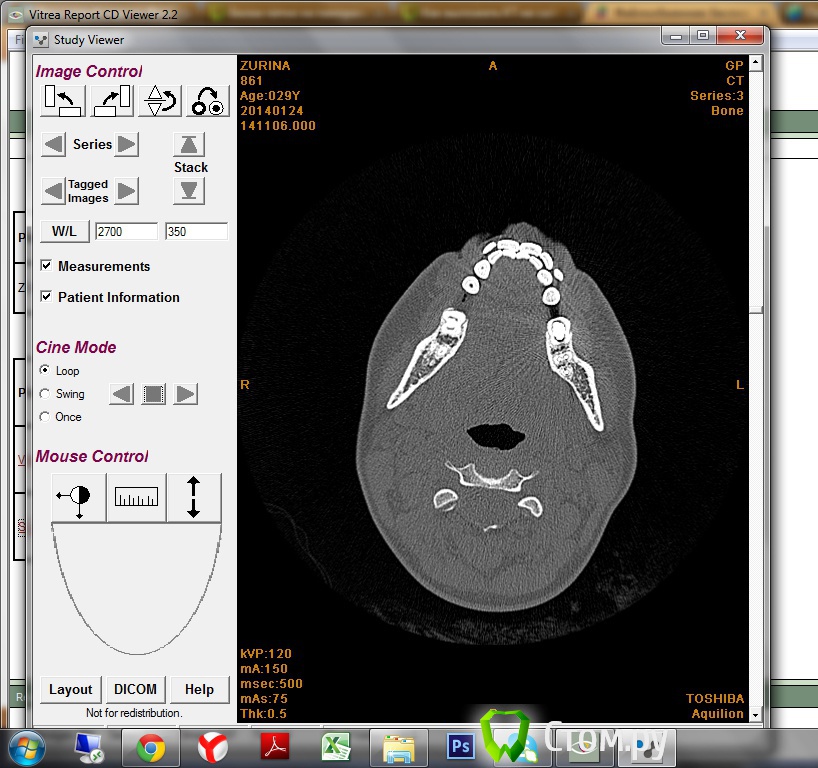

Natalya_msk Опубликовано 31 января, 2014 Автор Поделиться Опубликовано 31 января, 2014 Добрый вечер)) Долго пыталась понять какой именно скриншот мне нужен, но так и не смогла разобраться)Поэтому, пользуясь инструкцией сайта заархивировала нужную папку, она тут http://www.fayloobmennik.net/3536811 Всего 70 мб получилось. Описание выкладывала выше. Еще мне выдали снимки на пленке, как их сюда разместить - понятия не имею. ВОт один из скриншотов)) ничего не понятно)) В описании написано о двух образованиях. Ссылка на комментарий

Natalya_msk Опубликовано 12 февраля, 2014 Автор Поделиться Опубликовано 12 февраля, 2014 Ок, может так? Ссылка на комментарий